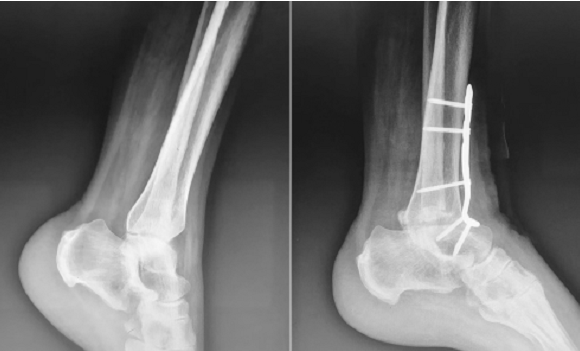

术前站立位踝关节正侧位 X 线片提示右踝重度骨性关节炎伴内翻畸形,测量胫距关节面夹角内翻 19°

有研究报道, 2~3 枚螺钉固定是融合关节的最佳选择,螺钉过少会导致融合关节受 压不足,而螺钉过多容易导致融合关节各方向受压不一致

采用踝关节前入路并使用3枚螺钉固定的踝关节融合术

优点:术后并发症发生率低,关节融合率高,疼痛和功能水平均有显著改善。

缺点:踝关节不愈合率较高,特别是骨质疏松的患者。